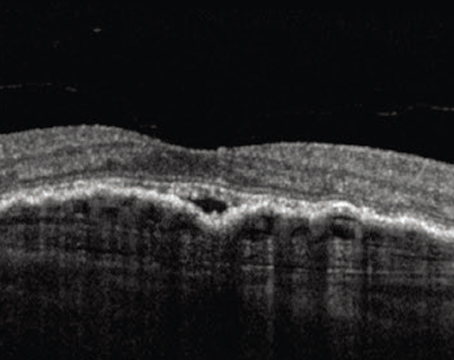

Can you recognize these novel OCT signs?

A review of characteristic optical coherence tomography findings that can help narrow or even confirm a novel diagnosis.